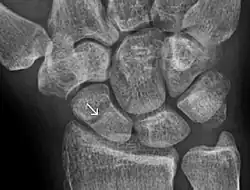

A more obvious scaphoid fracture on a scaphoid view X ray -

Radiolucency around a 12 days old scaphoid fracture that was initially barely visible.[13]